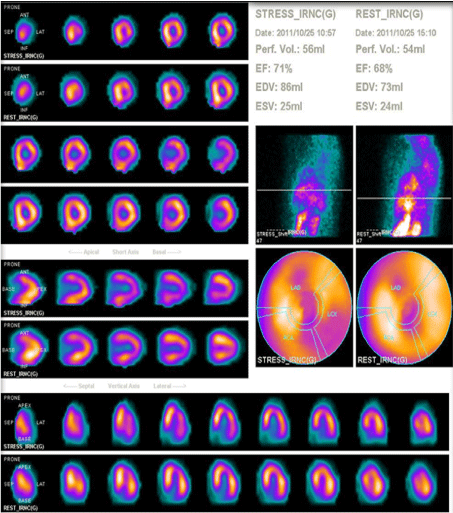

There were 34 ischemic segments in MPS and 46 in stress Echo among 493 segments of 29 patients. Both MPS and stress Echo pointed the same ischemic segments in 9 patients and tests were in agreement in 24 patients. However, only sixteen patients had angiography results (Table 2). The imaging results of the patients with angiography results were as follows; 6 patients with anterior, 6 patients with inferior, one patient with septum defect and three patient with normal perfusion were present also echo showed same regions hipokinesia in 9 patients and normal results in three scintigraphically normal patients. Angiography confirmed two test's results in 13/16 patients (Figure 1 represents a patient with similar results in both tests and confirmation result with angiography). Three patients with severe ischemia on MPS and stress Echo had slow flow pattern on angiography. The sensitivity, specificity, accuracy, negative, positive predictive values of the methods were 100%, 50%, 81%, 77%, and 100% for MPS and 90%, 60%, 81%, 77% and 90% for Echo respectively and are summarized in (Table 3) which shows very similar results for both tests. If we discard the patients with slow flow pattern results in angiography the sensitivity, specificity, accuracy, positive and negative predictive value of the MPS and Echo would be 67%, 43%, 69%, 60%, and 100% versus 100%, 71%, 85%, 75% and 100% respectively.

Figure 1b: Coronary angiography of the same patient also demonstrated the 70% narrowing of right coronary artery (arrow). View Figure 1b